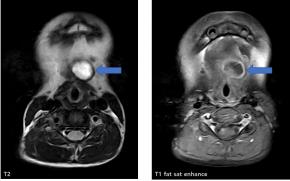

• Neck MRI also shows the complicated cystic lesion at the level of hyoid bone.